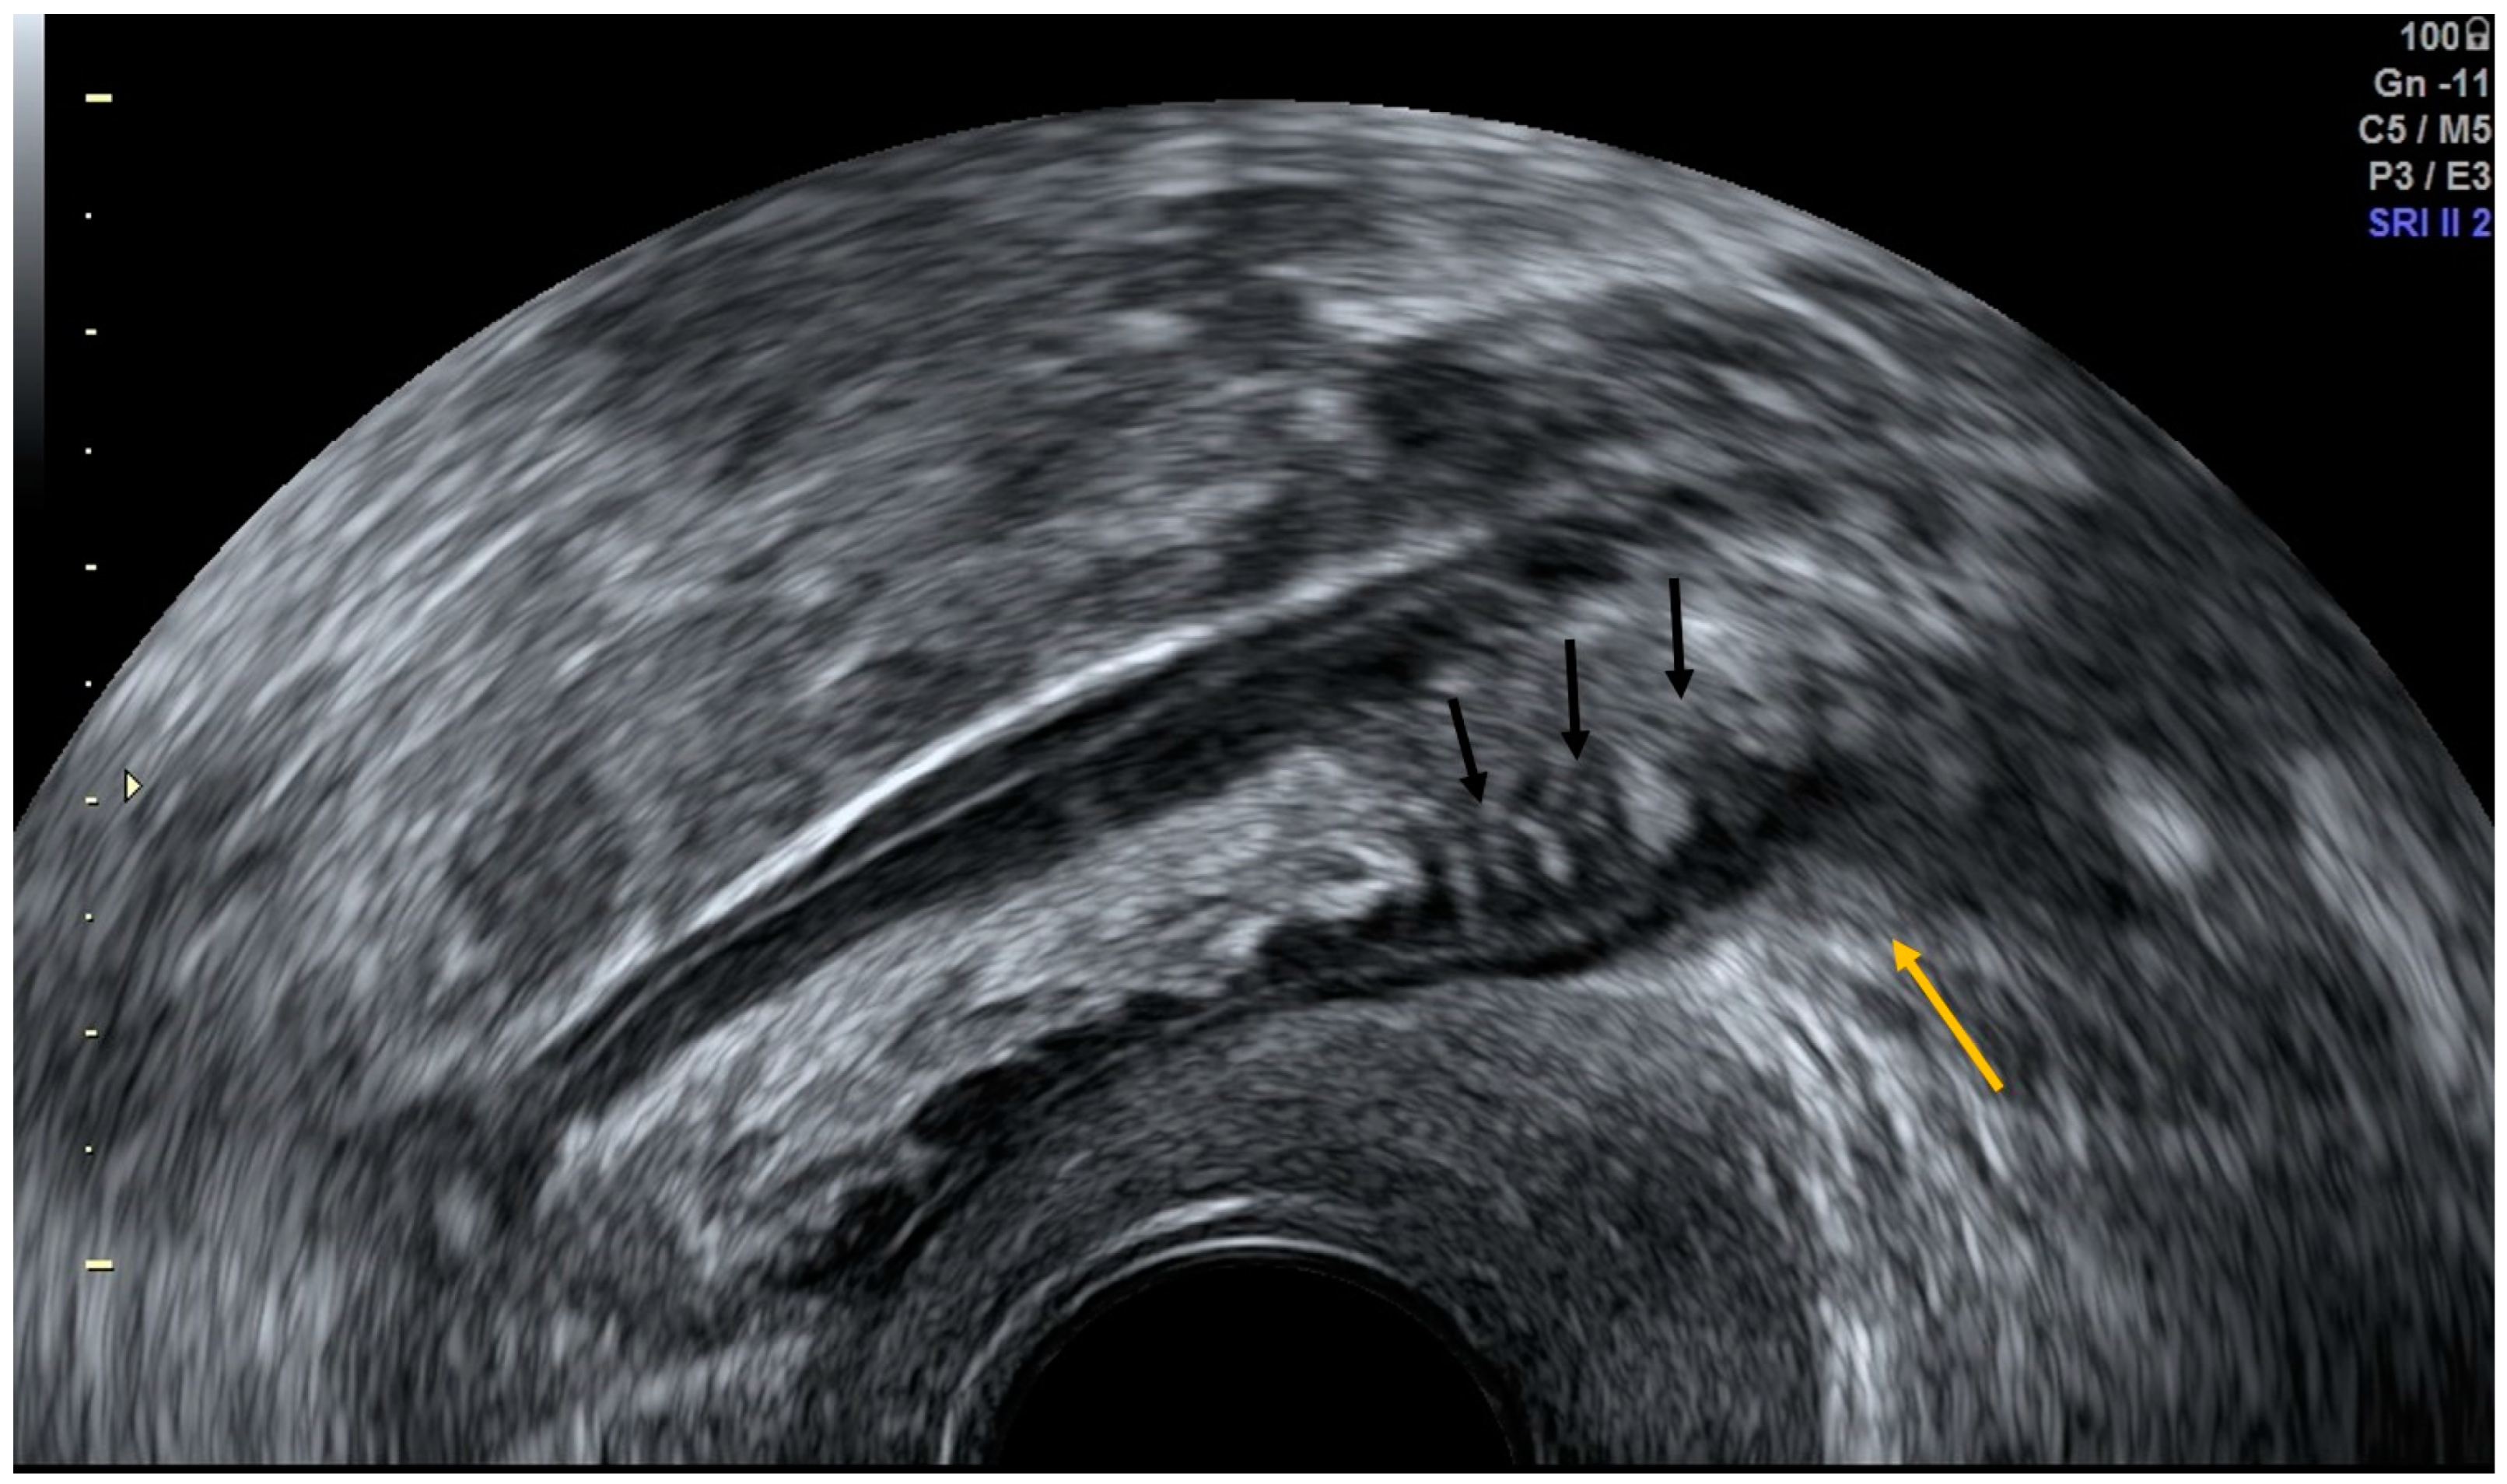

4.2. Thrombosis